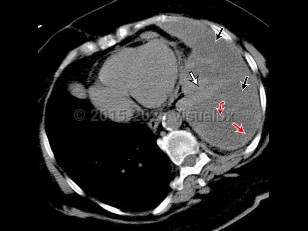

Clinically, effusions may be categorized as either transudates or exudates. Thoracentesis and laboratory evaluation as well as radiographic characteristics distinguish between these types.

Transudative pleural effusions are due to conditions in which there is an imbalance in hydrostatic and oncotic forces such as with heart failure, cirrhosis, or nephrotic syndrome.

Exudative effusions are due to inflammation from infection or noninfectious etiologies, injury, malignancy, and impaired lymphatic drainage. The primary method of distinguishing transudate from exudate is Light's criteria: